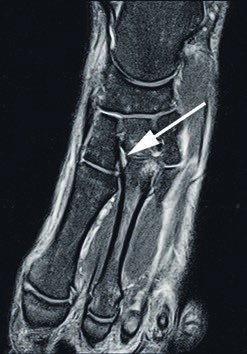

- Die Grad-I-Verletzung umschreibt eine Distorsion des Lisfranc-Bandes ohne mechanische Instabilität. Pa tienten mit dieser Verletzung klagen über Schmerzen in der Region des dorsalen Lisfranc’schen Bandes. Die Röntgenaufnahmen unter Belastung zeigen einen unauffälligen Befund. Kernspintomografisch lässt sich eine Signaländerung im Lisfranc-Bandkomplex nachweisen (siehe Abb. 2), jedoch keine Kontinuitätsunterbrechnung. Im 3‑Phasen-Skelettszintigramm zeigt sich eine Mehranreicherung 19 20.

Bei Athleten tritt eine Verletzung des Lisfranc-Bandkomplexes typischerweise auf, wenn der Fuß bei gleichzeitiger Plantarflexion und leichter Rotation axial belast et wird 43 44. Die Zerreißung des Lisfranc-Bandkomplexes führt zu einer tarsometatarsalen Dehiszenz mit Dislokation der Metatarsale-II-Basis nach dorsal 45. Nunley und Vertullo (2002) 46 gehen in ihren Untersuchungen davon aus, dass es bei der Grad-I-Verletzung lediglich zu einer Distorsion des Lisfranc’schen Bandes in Verbindung mit einer Verletzung der Gelenkkapsel kommt. Aufgrund des in sich noch stabilen Kapselbandkomplexes finden sich normale Belastungsaufnahmen; die Verletzung der dorsalen Bandanteile lässt sich jedoch kernspintomografisch nachweisen 47. Bei der Grad-II-Verletzung kommt es zusätzlich zu einer vollständigen Zerreißung der dorsalen Bandanteile. Radiologisch zeigt sich dies durch das Auseinanderweichen von Os metatarsale I und II auf den Röntgenaufnahmen unter Belastung. Da die plantaren Kapselbandanteile intakt bleiben, kommt es jedoch zu keinem Absinken des Längsgewölbes in der Seitenaufnahme. Bei Grad-III-Verletzungen liegt eine komplette Zerreißung der dorsalen und plantaren Kapselbandstrukturen mit einem instabilen ersten Tarsometatarsalgelenk vor. Dies zeigt sich radiologisch durch ein Absinken des Längsgewölbes 48.